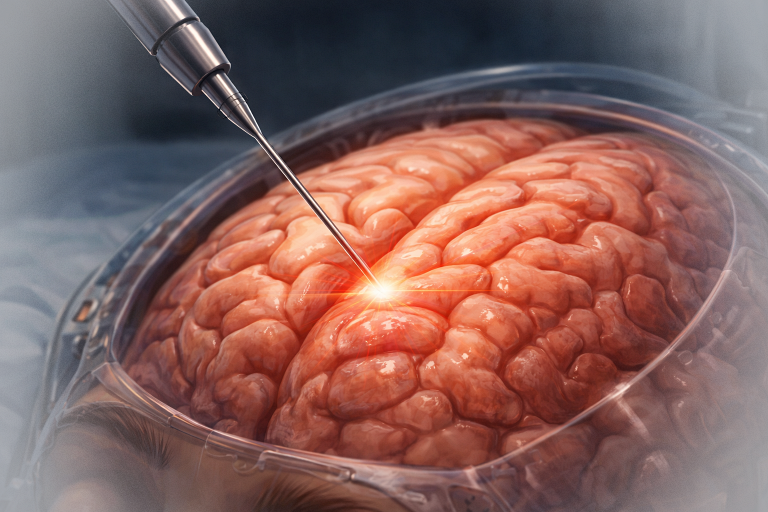

A. Tratamentul chirurgical:

Este principala formă de tratament pentru tumorile benigne și multe dintre cele maligne. Scop: rezecția completă cu margini negative, menținând funcțiile neurologice. Dacă tumora nu invadează meningele, riscurile neurologice sunt reduse; pe de altă parte, atunci când tumora se extinde și la nivelul durei mater sau chiar al creierului, este posibil ca excizia tumorii să fie subtotală sau parțială, pentru a proteja structurile nervoase.

Un timp important al operației îl reprezintă reconstrucția calotei craniene, care se face cu plăci ceramice customizate, mesh din titan sau ciment acrilic modelat pe loc. Uneori, datorită invaziei tegumentului, sunt necesare intervenții complexe de chirurgie plastică pentru refacerea defectului la nivelul scalpului.